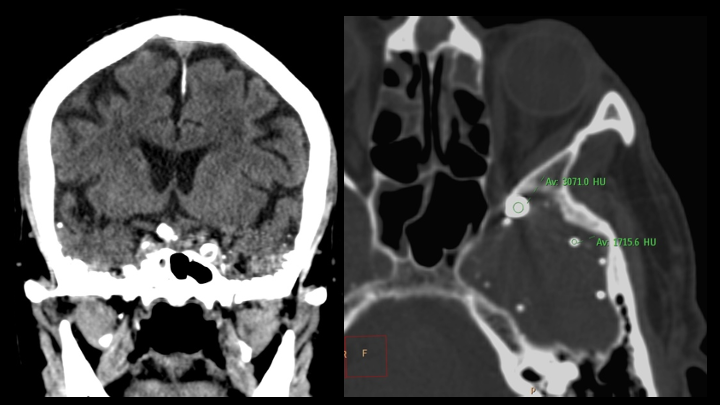

Los artefactos observados corresponden exclusivamente a material hiperdenso de probable origen metálico, generando artefactos lineales (streak artifacts), lo cual no limita la evaluación global del parénquima cerebral.

El material presenta densidad metálica y genera artefactos en estría (streak artifacts).